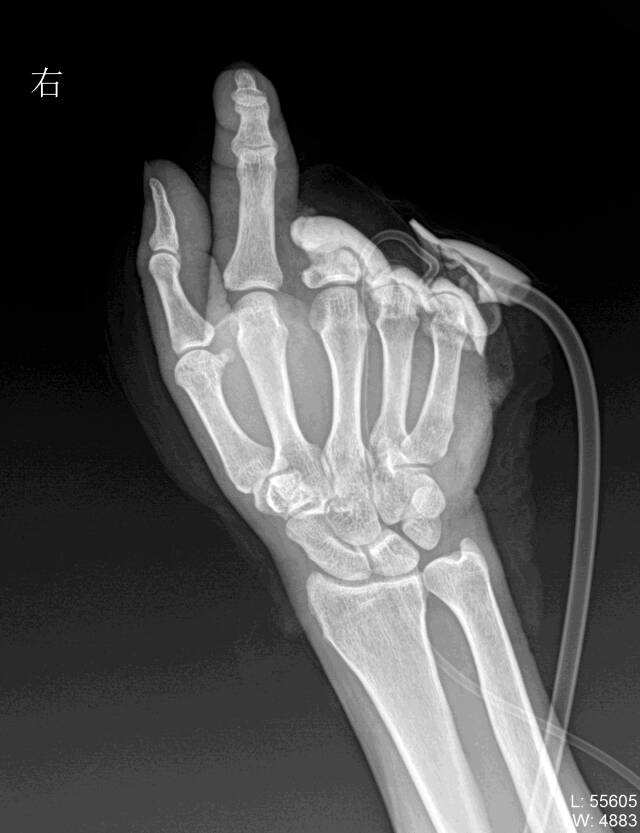

“接上的4根手指,现在吃饭、发信息都是没有啥问题,以后日常生活不成问题!我很满足了。”李先生一边笑着说,一边“展示”可活动的几根手指。李先生的左、右手的中指和无名指(一共4根手指)曾是脚趾,都是从他的脚上取下,移植到左、右手上的。

李先生今年49岁,一直在黄山的一家工厂里当操作工。2024年9月上午,机器皮带突然不转了,李先生用手扒了一下,机器又突然转动了起来,没想到,近4吨重冲床,重重的压了下来,他的左2-5指及右3-5指当时就被击掉了。

李先生在本地医院进行了前期的治疗后,即刻被家人送到了杭州邦尔骨科医院。“当时患者的左手的2-5指和右手3-5指离断,缺损非常严重。”杭州邦尔骨科医院手外科宋杰主任介绍。当时宋杰主任一边处理李先生的残端伤口,一边考虑为李先生将断指重新接上,可一问才得知,断指没了!

原来,李先生受伤后,疼痛难忍、血流不止,几个工友只忙着照顾他,没想着要找到、保存断指。考虑到缺的手指较多,以及功能的重要性,宋杰主任建议李先生将每个脚取2个脚趾进行再造,后期行左手第2指第5指延长术,通过这些方案来恢复他的手的完整性和功能。